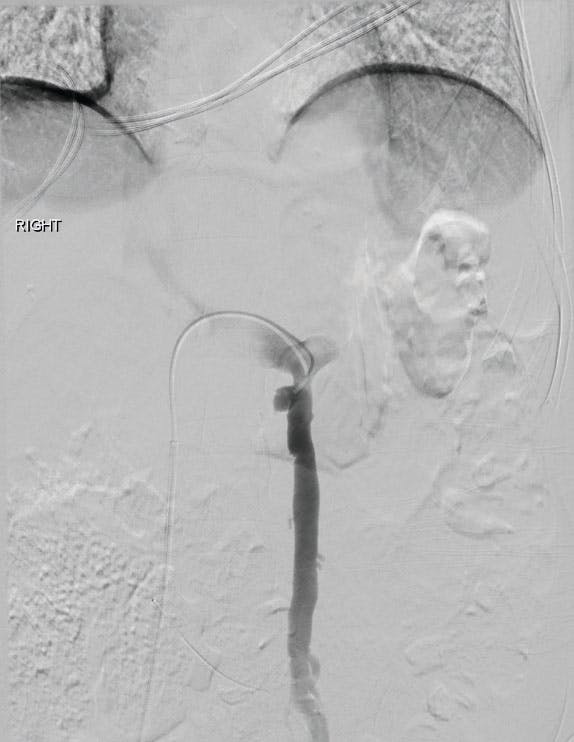

A male patient in his 60s presented with a symptomatic left-sided varicocele and was referred for gonadal vein embolization (Figure 1).

Figure 1. Angiogram showing left-sided varicocele.

Venous access was achieved via the right common femoral vein, and a 6-F, 45-cm Destination™ sheath (Terumo™ Interventional Systems) was advanced into the left renal vein. Selective catheterization of the left gonadal vein was performed using a 5-F Impress Bern™ catheter (Merit Medical™). Due to distal scrotal venous congestion, 4 mL of sodium tetradecyl sulfate was injected into the distal scrotal vascular bed prior to coil embolization.

Embolization of the left gonadal vein was performed using the Ruby XL platform. A Ruby Standard Coil was used for initial framing, followed by two Packing Coil XLs. A POD XL Coil was then deployed proximally to secure the coil mass. Completion venography demonstrated occlusion of the left gonadal vein without residual reflux (Figure 2).

Figure 2. Completion venogram.

This case demonstrates the use of the Ruby XL platform for gonadal vein embolization, allowing controlled coil deployment and dense packing across the treated segment.